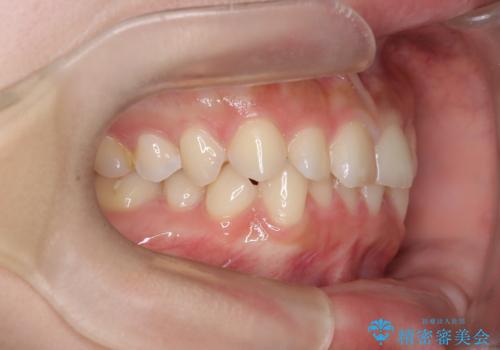

- 前歯のガタガタが気になるとのことでご相談いただきました。診察すると、歯列のスペースが不足し、前歯が重なっている状態でした。抜歯をせずに整えるため、歯と歯の間をわずかに削るIPR(歯列幅径削除)と、奥歯を後方へ動かす遠心移動を組み合わせてスペースを確保しながら並べる治療計画を立てました。

インビザラインを用いて歯を少しずつ移動させながら、IPRで微調整を行い、スペースを確保しました。また、奥歯を遠心移動させることで、前歯を自然な位置に並べることができました。治療後は、「ガタガタがなくなり、スムーズな歯並びになった」と患者様にもご満足いただきました。